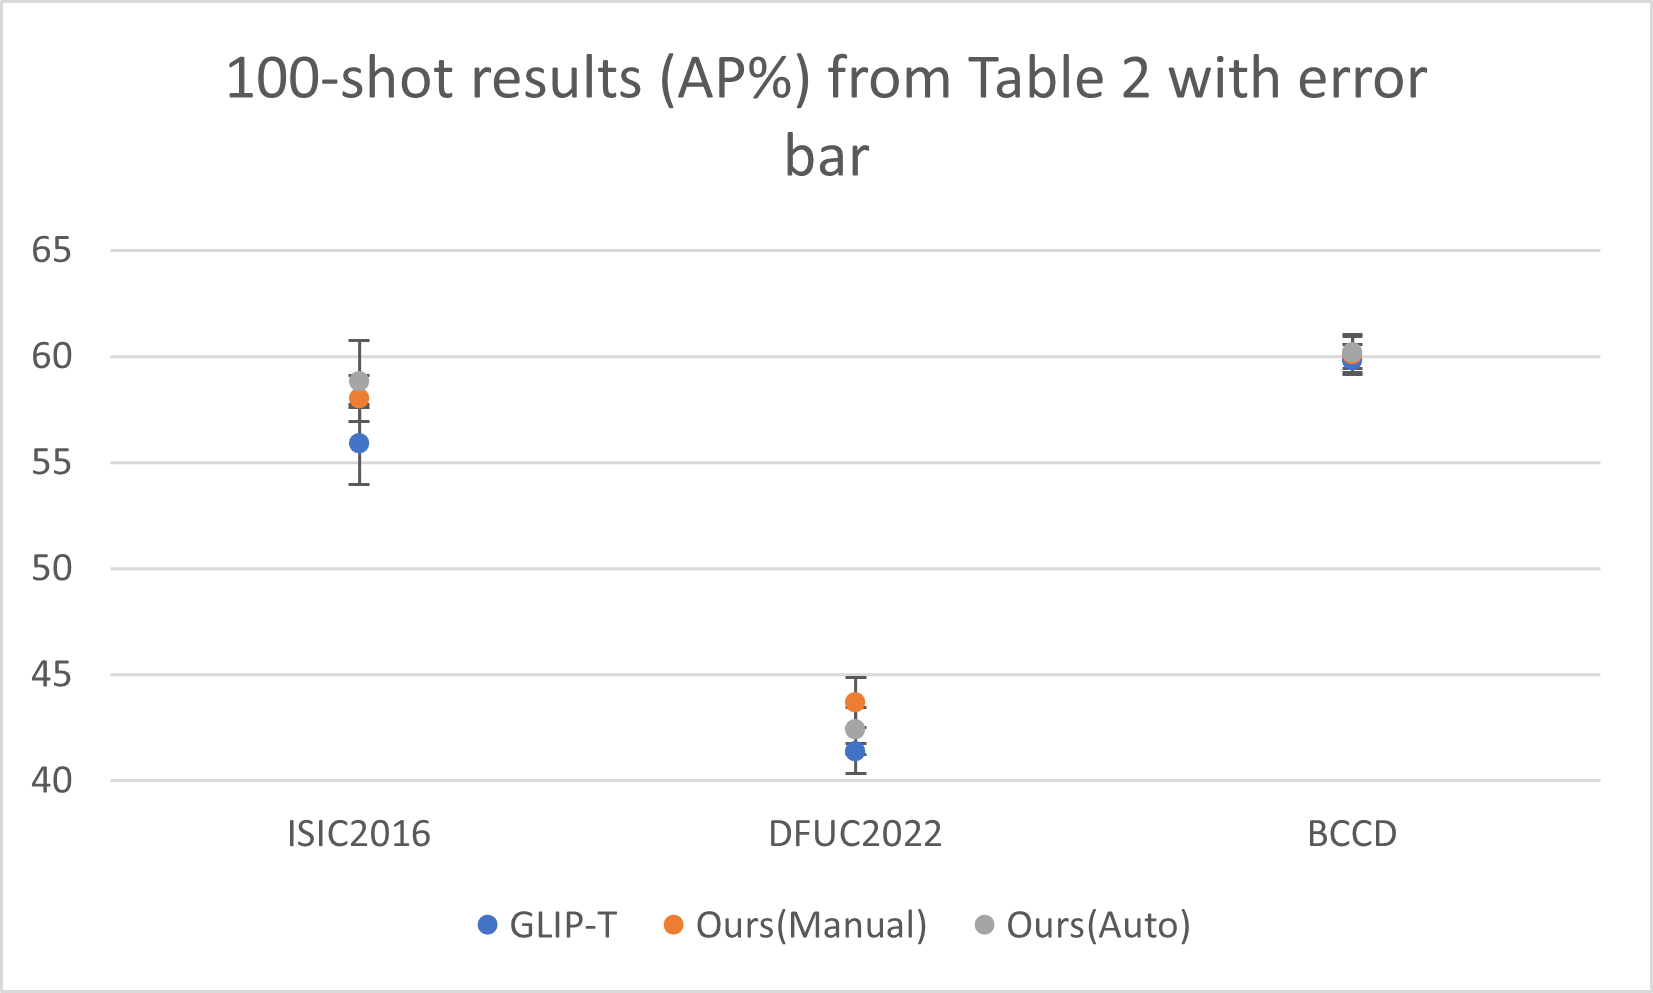

Transfer performance surpassing supervised methods To prove that text prompts are effective for cross-domain transfer, we conduct extensive experiments under both zero-shot domain transfer and supervised transfer (fine-tuning) settings. We include a series of supervised baselines: FasterRCNN, RetinaNet, and DyHead-L for comparisons. As illustrated in Figure 2, our full data fine-tuned models with well-designed medical prompts (dark blue) surpass the supervised baseline (e.g., DyHead-L in the figure) by a large margin across all datasets. Moreover, even zero-shot (brown) or 100-shot (sky blue) results on some datasets, e.g., CVC-300 and Luna-16, can rival the full data fine-tuned supervised models. The quantitative numbers are respectively shown in Table 2 for non-radiology datasets, Table 3 for polyp datasets, and Table 5 for radiology datasets. This is also supported by Figure 3 (right) where the VLMs significantly outperform the classical detection models with fully supervised learning, especially in few-shot settings.

Superior zero-shot transfer performance compared to the baseline Here, we provide strong evidence to show our approaches can empower the pre-trained VLM with remarkable zero-shot capability in the medical domain. As shown in Table 2 and Table 3, the prompts generated by our approaches tremendously improve the zero-shot performance of the GLIP models compared to the default ones. For example, on the polyp benchmarks, the out-of-box GLIP-T model only achieves an average AP of 4.1%, while the same model with our manually designed prompts reaches 41.3%. And this massive gain is not an exception. In addition, the models with well-designed prompts can reach an overall performance on par with the 100-shot fine-tuned baseline models on the polyp benchmarks (Table 3), and sometimes even rival the supervised baseline models trained with full-size data, e.g., on the CVC-300 dataset (69.9% AP for zero-shot v.s. 59.4% for Faster RCNN).

In this section, we demonstrate the standard deviation numbers and error-bar for our fine-tuning results. We use 3 different random seeds for our few-shot learning experiments to test whether our fine-tuning results are consistent across different random settings. The relative small standard deviation indicates that our method is not sensitive to the randomness.

| Method | ISIC 2016 | DFUC 2022 | Polyp | BCCD | Avg. | |

| 100-Shot | GLIP-T | 53.7 | ||||

| Ours (Manual) | 55.7 | |||||

| Ours (Auto) | 55.6 |